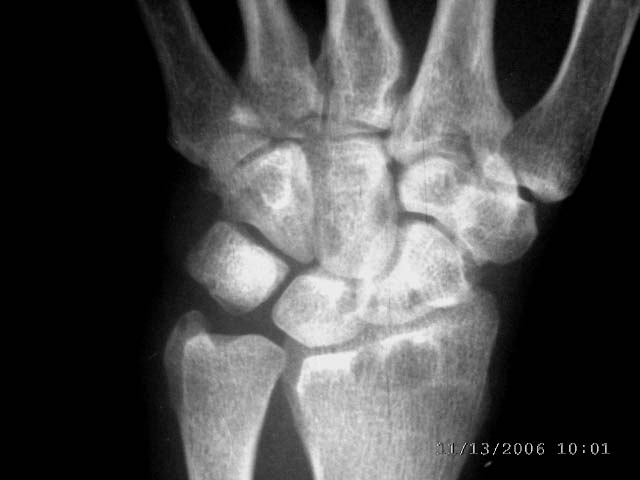

女45,右腕部夜间痛,晨僵感,局部皮温高,尺骨茎宊处轻度软组织肿胀2年余。自小感觉右手温觉和痛觉差。

右桡骨下端、舟骨,月骨,三角骨,头状骨,尺骨茎突均可见囊状低密度影,尺侧软组织似稍肿胀。患者虽然为女45,右腕部夜间痛,晨僵感,局部皮温高,尺骨茎宊处轻度软组织肿胀2年余。但类风湿似乎不象,我认为应考虑结核。

右桡骨下端、舟骨,月骨,三角骨,头状骨,尺骨茎突均可见囊状低密度影,尺侧软组织似稍肿胀。患者虽然为女45,右腕部夜间痛,晨僵感,局部皮温高,尺骨茎宊处轻度软组织肿胀2年余。我认为应考虑结核。(依据可见吻状破坏),自小感觉右手温觉和痛觉差,症状像神经性骨关节病,但影像不像。

再补充点鉴别诊断思路:透析性骨关节病.透析性骨关节病容易在腕关节处出现淀粉样变性,造成出现腕管综合症,实际本病例的临床症状就是腕管综合症的表现,腕骨也可以出现同本病例的类似x光表现,当然透析病史很重要,且一般要10年以上出现透析性骨关节病的可能性大.实际上本病例很早即有症状,故骨内腱鞘囊肿形成较早,范围可能没现在广而已.